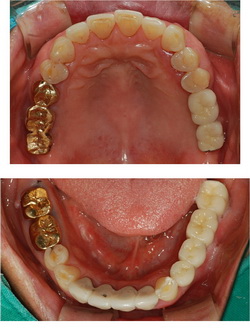

| 2Â÷ ¼ö¼ú ÈÄ ÀÕ¸öÀÌ ¾Æ¹°¸é º¸Ã¶¹°À» Á¦ÀÛÇÏ°Ô µË´Ï´Ù. ¿©±â¼ ºÎÅÍ´Â ÀÏ¹Ý º¸Ã¶¹° Á¦ÀÛ°ú µ¿ÀÏÇÏ¸ç µû¶ó¼ ±Ý´Ïµµ °¡´ÉÇϰí Ä¡¾Æ»öÀÌ ³ª´Â º¸Ã¶¹°µµ ¸ðµÎ °¡´ÉÇÕ´Ï´Ù. º¸Ã¶¹°Àº ´ëºÎºÐ °íÁ¤µÇ´Â º¸Ã¶¹°À» Á¦ÀÛÇϳª, Ä¡¾Æ°¡ Çϳªµµ ¾ø´Â °æ¿ì¿¡ ÀÖ¾î¼ ÀÓÇöõÆ® °³¼ö¿¡ µû¶ó¼ Ʋ´Ï Çü½ÄÀ¸·Î Á¦ÀÛÇÏ´Â °æ¿ìµµ ÀÖ½À´Ï´Ù. Ʋ´Ï Çü½ÄÀ¸·Î Á¦ÀÛÇÏ°Ô µÇ´õ¶óµµ ¾Ã´Â Èû°ú À¯Áö·ÂÀº ÀÏ¹Ý Æ²´Ïº¸´Ù ¿ì¼öÇÕ´Ï´Ù. |

| ÀÓÇöõÆ®´Â ¾Ã´Â ÈûÀ» ¿ø»óÅ·Πȸº¹½ÃÄÑ ÁÝ´Ï´Ù. ÀÏ¹Ý Æ²´Ï¸¦ ÇÏ½Ç °æ¿ì¿¡´Â ¾Ã´Â ÈûÀ» 50%µµ ȸº¹ÇÏ±â ¾î·Æ½À´Ï´Ù. µû¶ó¼ ÀÏ¹Ý Æ²´Ï¸¦ Àß ¾²°í °è¼Ì´ø ºÐµµ ÀÓÇöõÆ®·Î ±³Ã¼ÇÏ½Ã¸é ¾Ã´Â ÈûÀ» 2¹è ÀÌ»ó Çâ»ó½ÃŰ½Ç ¼ö ÀÖ½À´Ï´Ù.

ÀÓÇöõÆ®´Â ½±°Ô Å»¶ôÇϴ Ʋ´Ï¸¦ Àâ¾ÆÁÖ¾î Æ²´Ï°¡ ¿òÁ÷ÀÌÁö ¾Ê°í Àß ±â´ÉÇÒ ¼ö ÀÖ°Ô µµ¿ÍÁÝ´Ï´Ù. ÀÏ¹ÝÆ²´Ï Áß¿¡¼ ƯÈ÷ ¾Æ·¡ Ʋ´Ï´Â Ʋ´Ï°¡ ¾ÈÂøµÇ´Â ¸éÀûÀÌ À۾Ƽ ½±°Ô Å»¶ôµÇ°í ¿òÁ÷¿©¼ ÅëÁõ°ú ÀúÀÛ±â´É Àå¾ÖÀÇ ¿øÀÎÀÌ µË´Ï´Ù. À̸¦ ÀÓÇöõÆ®¸¦ ÀÌ¿ëÇÑ Æ²´Ï ¶Ç´Â ÀüºÎ ÀÓÇöõÆ®·Î ±³Ã¼ÇÏ½Ã¸é ´õ Æí¾ÈÇÏ°Ô À½½Ä¹°À» µå½Ç ¼ö ÀÖ½À´Ï´Ù.